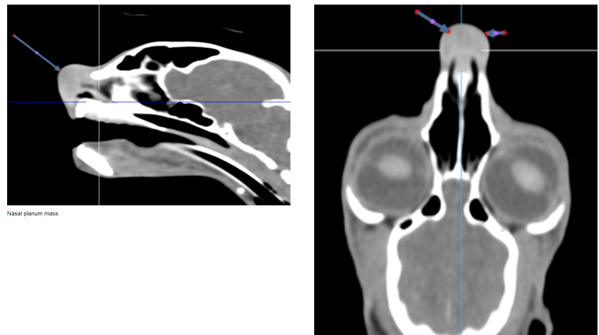

CT head – swelling of the nasal planum without deeper involvement in the nasal cavity or cranium.